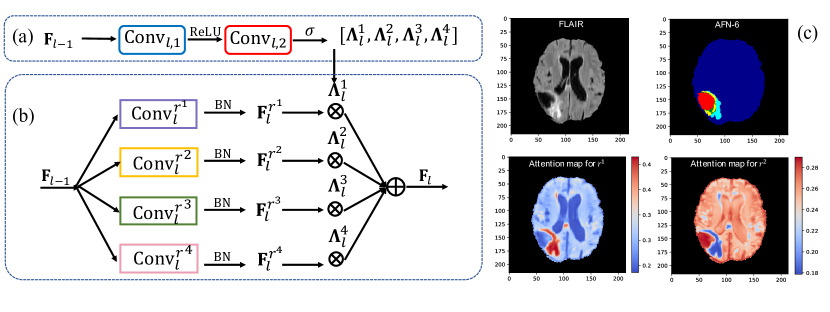

Figure 1: An autofocus convolutional layer with the number of candidate dilation rates K=4𝐾4K=4. (a) The attention model. (b) A weighted summation of activations from parallel dilated convolutions. (c) An example of attention maps for a small (r1superscript𝑟1r^{1}) and larger (r2superscript𝑟2r^{2}) dilation rate. The first row is the input and the segmentation result of Afn-6 (described in Sec. 2.3). The second row shows how the module ‘zooms out’ for more context when processing large or ambiguous structures.

Unambiguously classifying different objects in an image is likely to require different combinations of local and global information. For example, large structures may be better segmented by processing a large receptive field ϕlsubscriptbold-italic-ϕ𝑙\bm{\phi}_{l} at the expense of fine details, while small objects may require focusing on high resolution local information. Consequently, architectures that statically define multi-scale processing may be suboptimal. Our adaptive solution, the autofocus module, is summarized in Fig. 1 and formalized in the following.

Given activations of the previous layer Fl1subscriptF𝑙1\textbf{F}_{l-1}, we capture multi-scale information by processing it in parallel via K𝐾K convolutional layers with different dilation rates rksuperscript𝑟𝑘r^{k}. They produce K𝐾K tensors FlrksubscriptsuperscriptFsuperscript𝑟𝑘𝑙\textbf{F}^{r^{k}}_{l} (Fig. 1(b)), each set to have same number of channels C𝐶C. They detect patterns at K𝐾K different scales which we merge in a data-driven manner by introducing a soft attention mechanism [1].

Within the module we construct a small attention network (Fig. 1(a)) that processes Fl1subscriptF𝑙1\textbf{F}_{l-1}. In this work it consists of two convolutional layers. The first, Convl,1subscriptConv𝑙1\textbf{Conv}_{l,1}, applies 3×\times3×\times3 kernels, produces half the number of channels than those in Fl1subscriptF𝑙1\textbf{F}_{l-1} (empirically chosen) and is followed by a ReLU activation function f𝑓f. The second, Convl,2subscriptConv𝑙2\textbf{Conv}_{l,2}, applies 1×\times1×\times1 filters and produces a tensor with K𝐾K channels, one per scale. It is followed by an element-wise softmax σ𝜎\sigma that normalizes the K𝐾K activations for each voxel to add up to one. Let this normalized output be 𝚲l=[𝚲l1,𝚲l2,,𝚲lK]W×H×D×Ksubscript𝚲𝑙superscriptsubscript𝚲𝑙1superscriptsubscript𝚲𝑙2superscriptsubscript𝚲𝑙𝐾superscript𝑊𝐻𝐷𝐾\mathbf{\Lambda}_{l}=[\mathbf{\Lambda}_{l}^{1},\mathbf{\Lambda}_{l}^{2},\cdots,\mathbf{\Lambda}_{l}^{K}]\in\mathbb{R}^{W\times H\times D\times K}. Formally:

In the above, 𝚲lkW×H×Dsuperscriptsubscript𝚲𝑙𝑘superscript𝑊𝐻𝐷\mathbf{\Lambda}_{l}^{k}\in\mathbb{R}^{W\times H\times D} is an attention map that corresponds to the k𝑘k-th scale. For any specific spatial location (voxel), the corresponding K𝐾K values from the K𝐾K attention maps 𝚲lksuperscriptsubscript𝚲𝑙𝑘\mathbf{\Lambda}_{l}^{k} can be interpreted as how much focus to put on each scale. Thus the final output of the autofocus layer is computed by fusing the outputs from the parallel dillated convolutions as follows:

where \cdot is an element-wise multiplication. Note that the attention weights 𝚲lksuperscriptsubscript𝚲𝑙𝑘\mathbf{\Lambda}_{l}^{k} are shared across all channels of tensor FlrksuperscriptsubscriptF𝑙superscript𝑟𝑘\textbf{F}_{l}^{r^{k}} for scale k𝑘k. Since the attention maps are predicted by a fully convolutional network, different attention is predicted for each voxel, driven by the image context for the optimal choice of scale (Fig. 1(c)).